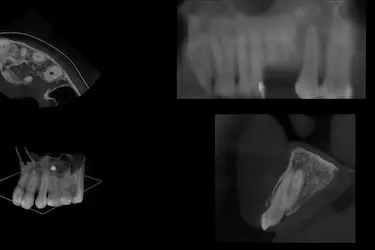

La principal ventaja de hacerse un TAC dental 3D es que permite a nuestros especialistas realizar cortes bidimensionales y tridimensionales de las imágenes obtenidas de tu boca.

Gracias a lo que se ve en una radiografía TAC 3D, el odontólogo pueden averiguar fácilmente:

- Cuál es la densidad y, en consecuencia, la calidad del hueso de la mandíbula.

- Dónde se encuentran los nervios y los vasos sanguíneos con total precisión.

- Qué piezas dentales y estructuras se encuentran en mal estado.

Con las fotos de un TAC dental se pueden ver imágenes detalladas de los dientes, huesos maxilares, mandíbula, raíces dentales y tejidos de alrededor, permitiendo un diagnóstico preciso.